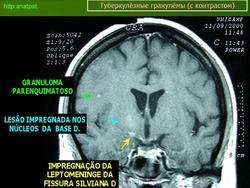

Менингеальный больной туберкулёзом на фоне ВИЧ.

anatpat.unicamp

Приложения:

131129-1.jpg131129-2.jpg131129-3.jpg131129-4.jpg131129-5.jpg131129-6.jpg131129-7.jpg131129-8.jpg131129-9.jpg131129-12.jpg131129-13.jpg131129-14.jpg131129-15.jpg131129-16.jpg131129-17.jpg131129-18.jpg131129-19.jpg131129-20.jpg131129-21.jpg131129-22.jpg131129-23.jpg131129-24.jpg